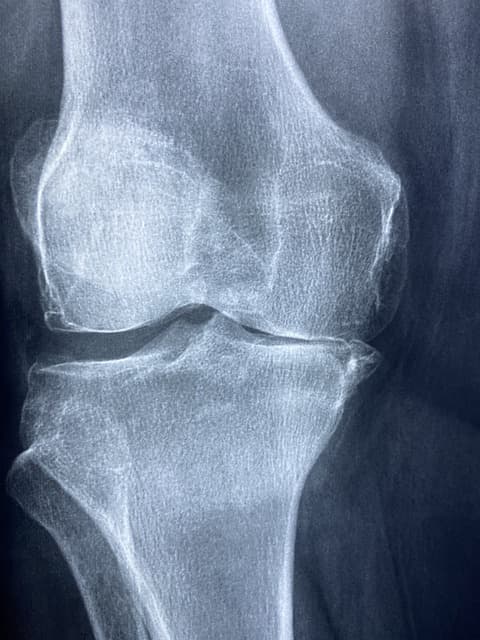

류마티스 관절염은 면역 체계가 자신의 신체 조직을 공격하여 관절에 염증을 일으키는 자가면역 질환입니다. 주요 증상으로는 관절의 통증, 부기, 뻣뻣함이 있으며, 특히 아침에 더 심한 경직이 나타나는 것이 특징입니다. 이 질환은 손, 발, 손목과 같은 작은 관절에서 시작되며, 심하면 심장, 폐, 혈관 등 다른 기관에도 영향을 줄 수 있습니다.

류마티스 관절염의 약물 치료는 증상 완화와 질병 진행 억제에 중점을 둡니다. 비스테로이드성 소염제는 통증과 염증을 완화하며, 질병조절 항류마티스제는 관절 손상을 예방하고 염증을 억제하는 데 효과적입니다. 생물학적 제제는 특정 면역 반응을 억제하여 질병 진행을 늦추는 데 사용됩니다. 이러한 약물들은 의사의 처방에 따라 사용해야 하며, 부작용을 줄이기 위해 정기적인 검진이 필요합니다.